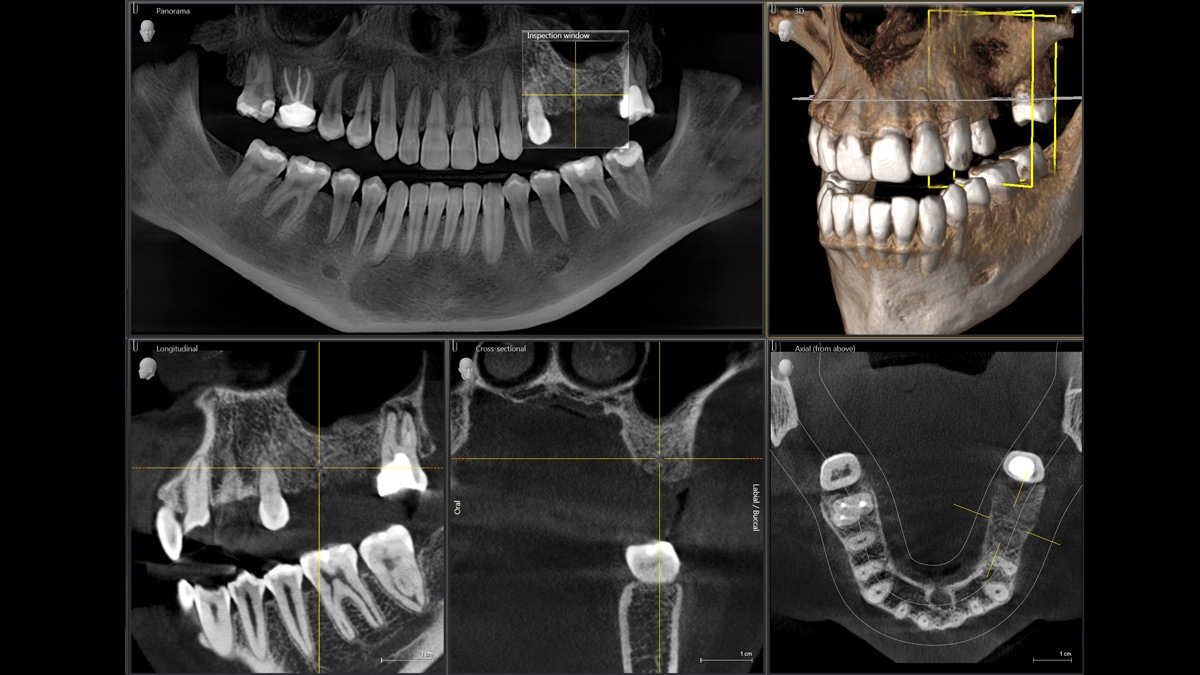

Мы разработали состоящую из 10 пунктов концепцию простого позиционирования пациента во время рентгенографии. Наша концепция включает: высокое качество изображения и комфорт для пациента и ассистента. Эта концепция поддерживает и предоставляет инструменты, необходимые для получения высококачественных изображений для анализа лечения, она направлена на эргономику и комфорт для пациента и ассистента. Например, патентованная автоматическая окклюзионная накусочная пластина обеспечивает правильный наклон головы пациента; позиционирование пациента по франкфуртской горизонтали, совместно с трехточечной фиксацией головы и наличием опор для рук обеспечивает стабильное позиционирование, ограничивая коррекцию без необходимости.